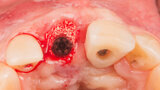

Immediate placement and restoration of a Straumann BLX implant replacing maxillary incisors